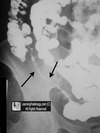

Cullens sign

Peri-umbilical ecchymosis

Acute pancreatitis